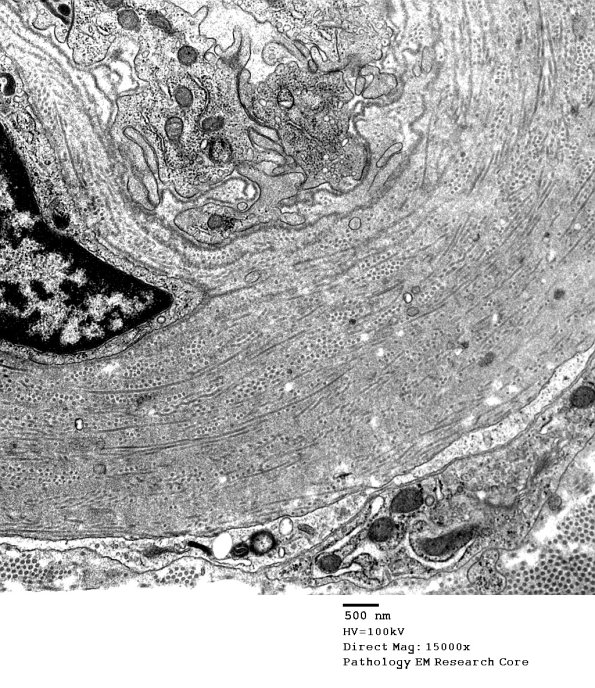

Progressively higher magnifications of the wall of this vessel shows it is composed of collagen oriented in longitudinal and circumferential patterns. (electron micrographs)